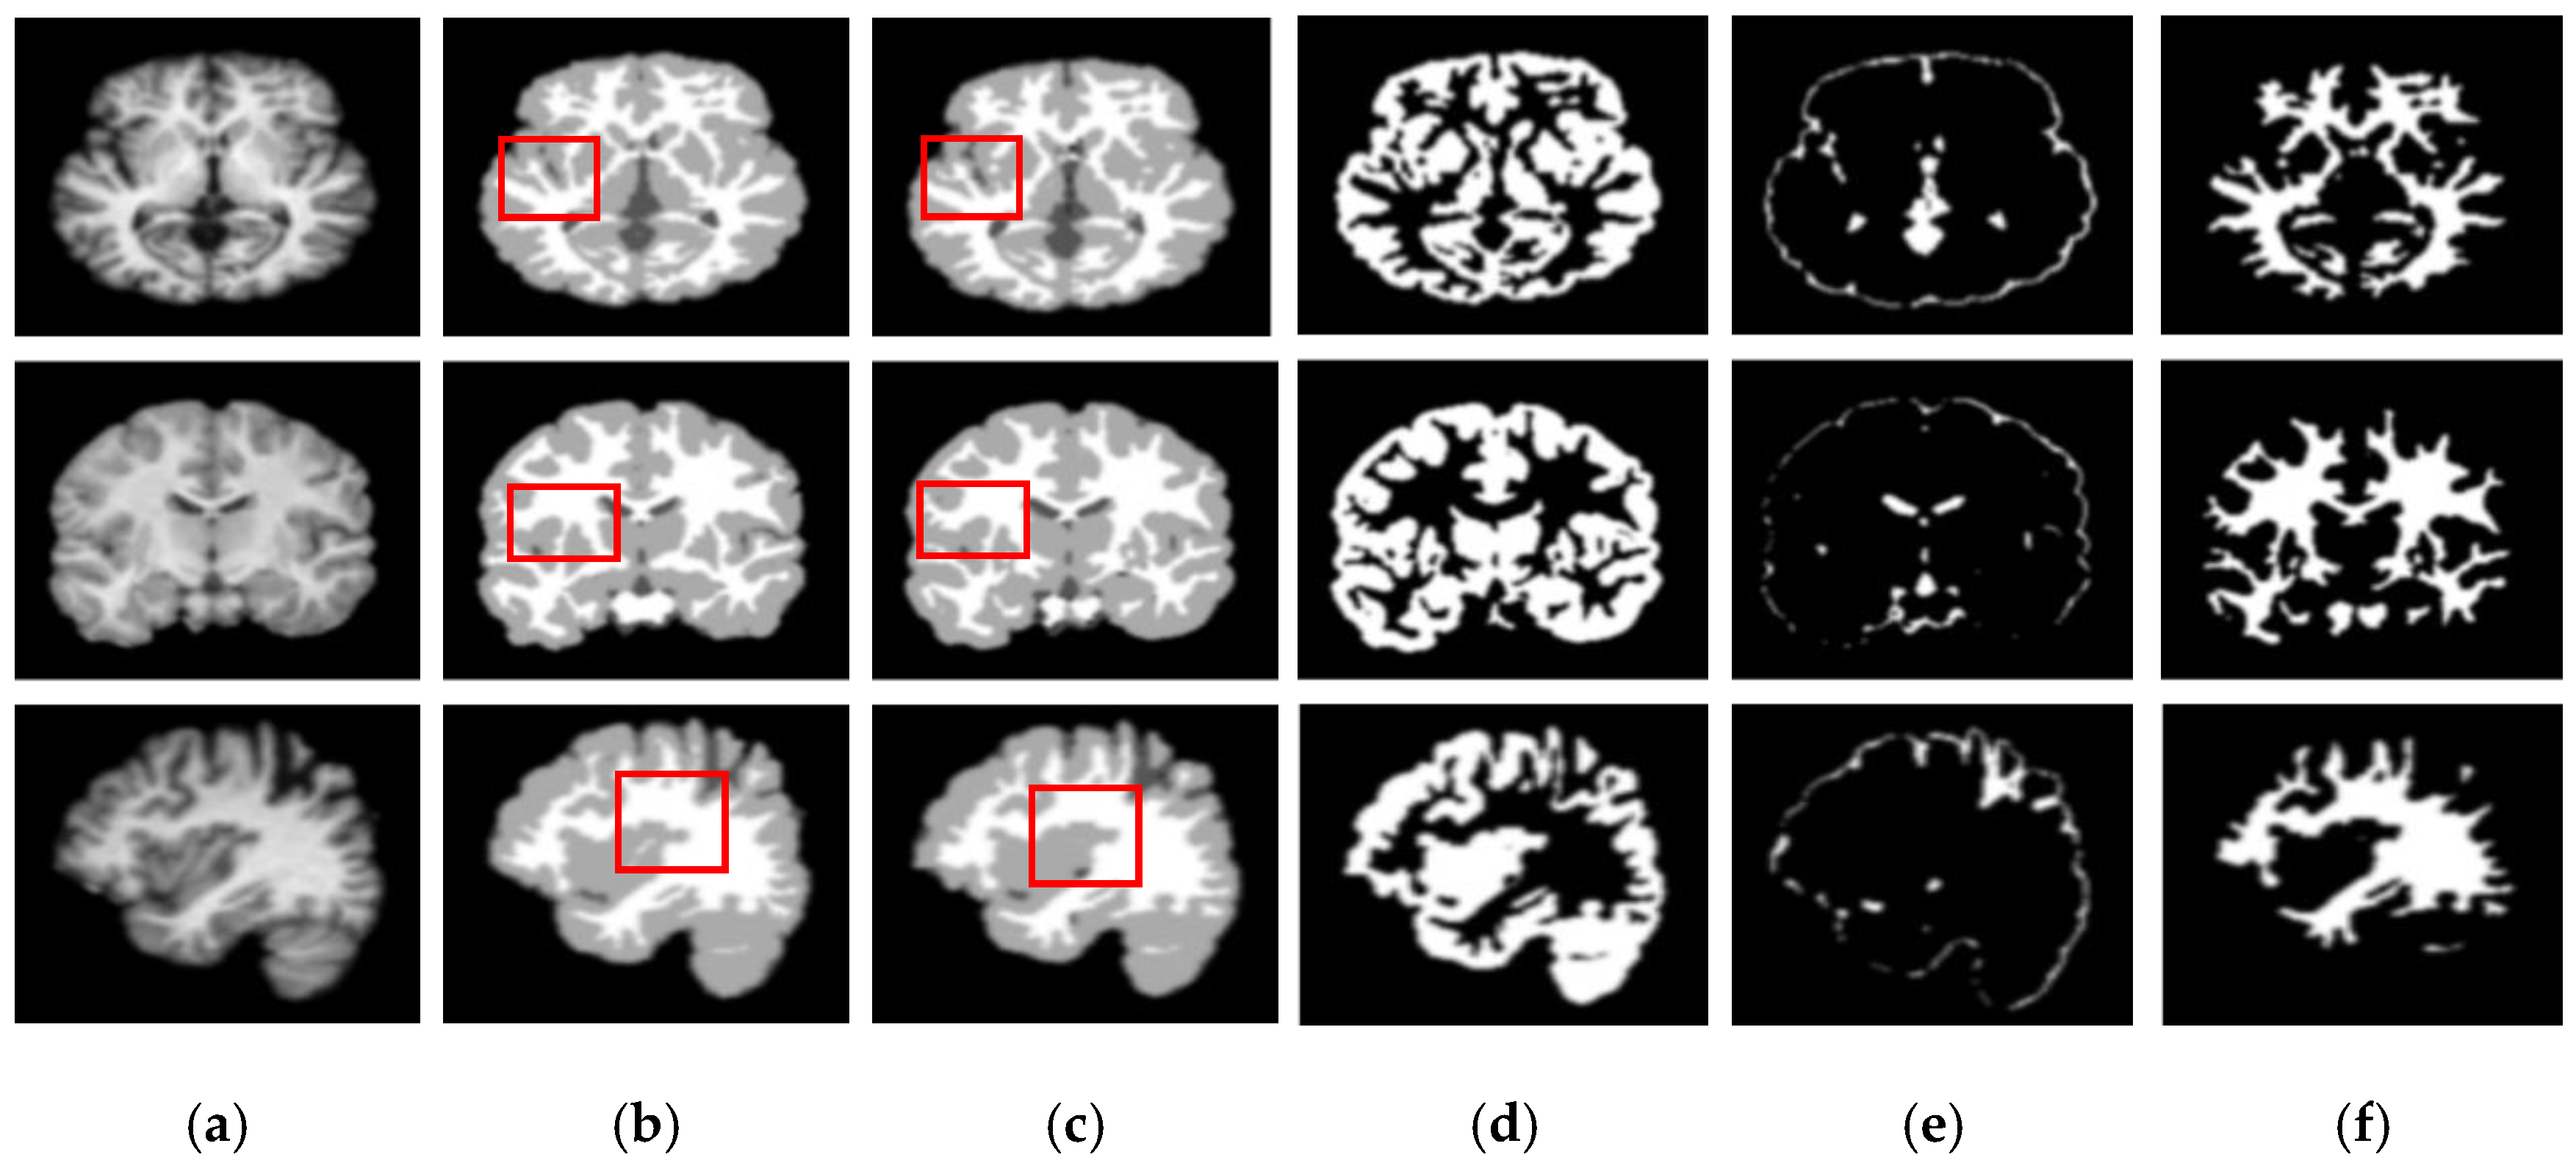

Figure 5 and Figure 6 show the segmentation results for the axial, coronal, and sagittal planes of the OASIS and IBSR datasets, respectively. The figures show that the proposed approach achieves well-segmented performances for GM, WM, and CSF of the brain MRI on both datasets. The axial plane shows the most informative details in the central slices of the MRI compared to the other planes. Thus, the segmentation results for the axial planes show the segmentation performance most effectively. In addition, the highlighted boxes in Figure 5 and Figure 6 show that the quality of sagittal and coronal images is highly promising without any difference in every detail. From the results of Figure 5 and Figure 6, it can be inferred that the proposed method can extract complicated pattern features from all three planes.

Figure 6.

Segmentation results for the axial, coronal, and sagittal planes of the brain MRI image (top to bottom) on the IBSR dataset using the proposed method. (a) Original input images, (b) ground truth segmentation map, (c) their predicted segmentation map obtained by using the proposed method, (d) predicted GM (binary map), (e) predicted CSF (binary map), (f) predicted WM (binary map).